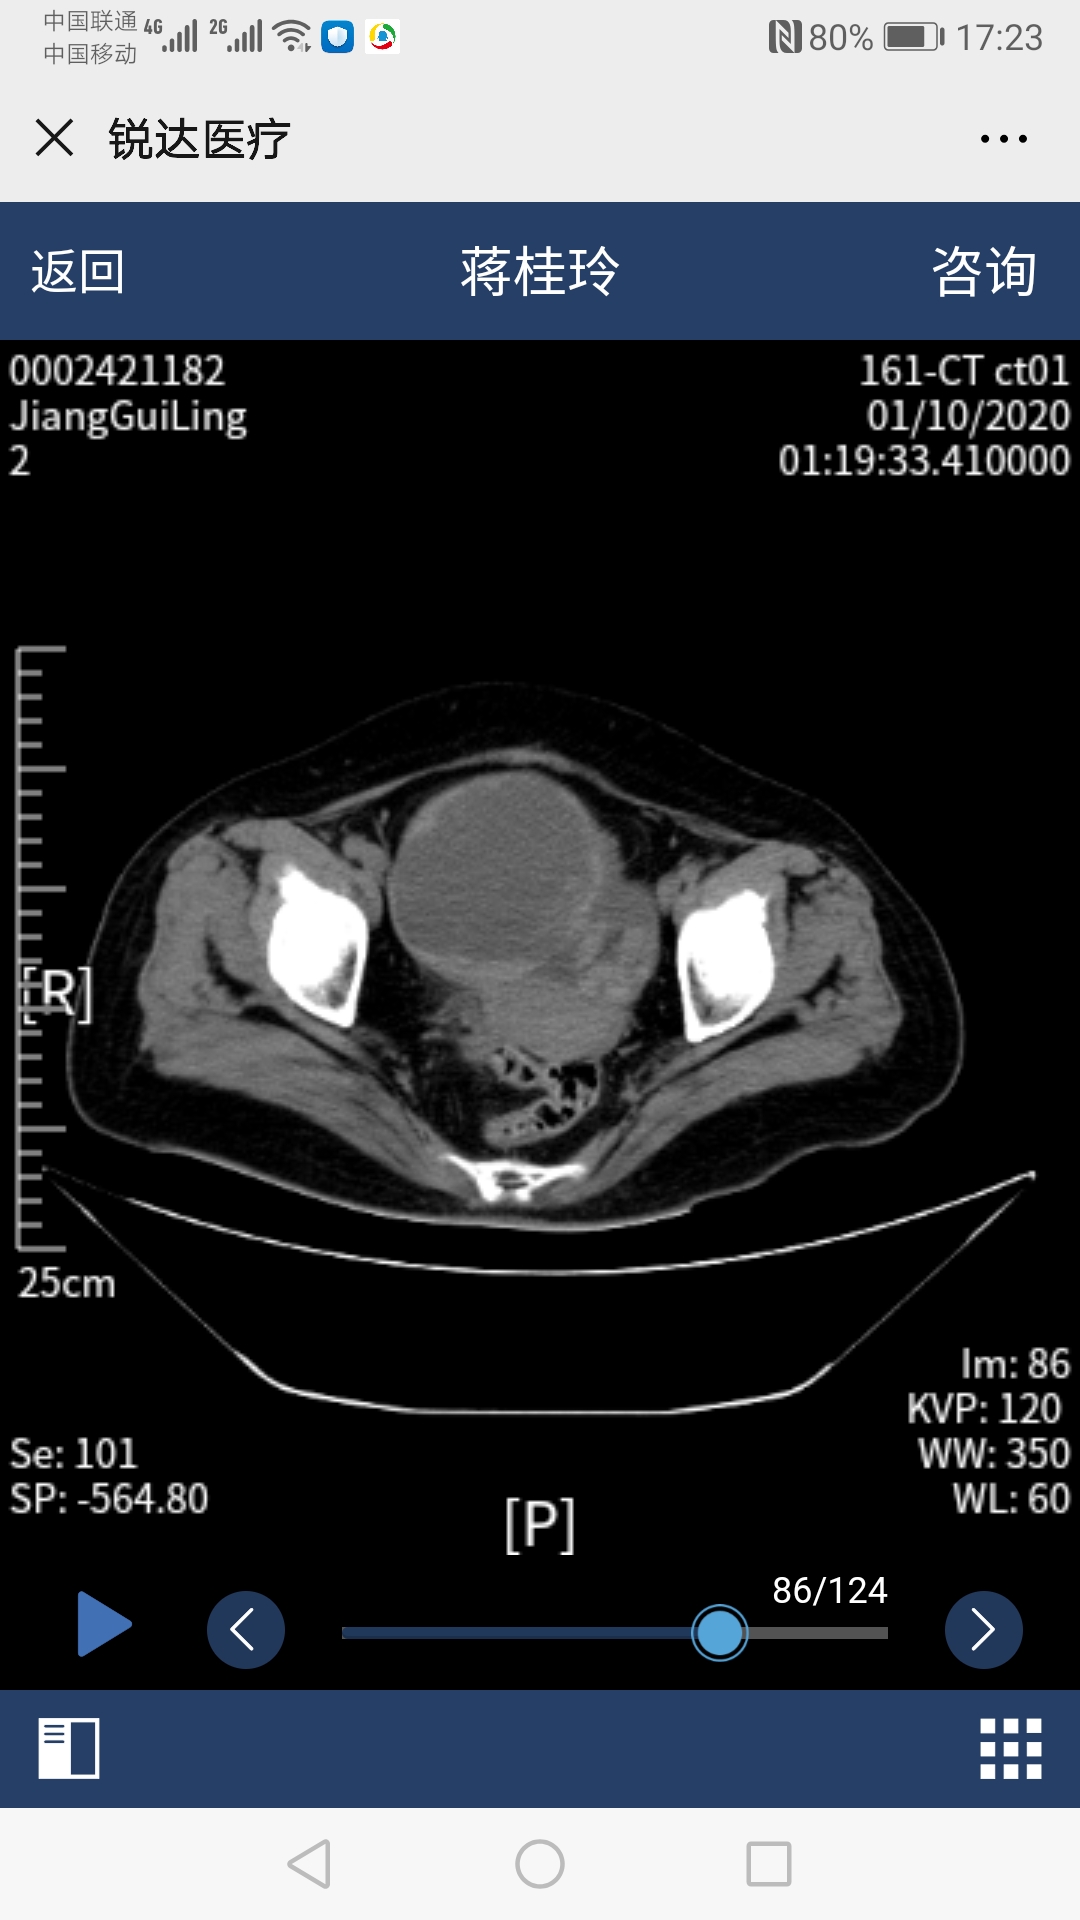

54岁的蒋阿姨最近常常觉得腹部胀痛,没有食欲,排便困难。肚子上出现一个包块,且越来越大。在当地医院就诊发现腹部有一个巨大的囊性肿物(12cm*8cm*12.6cm),但却同时检查出了患有先天性心脏病--房间隔缺损,并且已经出现了右心衰竭和明显肺动脉高压症状,加上既往冠心病、糖尿病、肾结石等多种疾病,医生在询问病史、完善检查之后说道:"你这手术风险太大,还是到别的医院试一试吧,我们这里不敢做"。蒋阿姨先后在省内多家大医院奔波求医,有的建议外科手术治疗腹部肿块,但因有房间隔缺损等多种疾病,风险较大;有的建议先做房间隔缺损手术,但术后需抗栓治疗6个月,期间不方便行腹部肿块手术,那就要继续忍受6个月的痛苦;总之,没有找到合适的方案。 正在蒋阿姨痛苦万分的时候,她听说哈医大四院心内科*巍杨**主任技术高超,医院整体实力雄厚,可能有更好的方案。蒋阿姨一家慕名来到了心内七病房,看着在病床上挣扎的蒋阿姨,杨主任急患者之所急,积极组织全院会诊,在院领导及医务科的协调下,邀请心内科、妇科、普外科、消化科、肿瘤科、心脏超声科、彩超室参与患者病情讨论,专家们建议患者先*房行**间隔缺损封堵术,再进行腹部囊肿穿刺术。手术于会诊后立即实行,*巍杨**主任、张明宇主任及心内科彩超室薛莉主任采用微创方法实施房间隔缺损封堵术,术后一周由彩超室董晓秋主任和刘瑞松医师为她做了腹部巨大囊性肿物穿刺引流术,3天共引流出1000毫升血性液体,后成功撤出引流管,蒋阿姨腹部胀痛等不良感觉消失。在心内七病房全体医护人员的悉心照料,蒋阿姨术后恢复良好,没有出现任何并发症及不良反应,顺利出院。